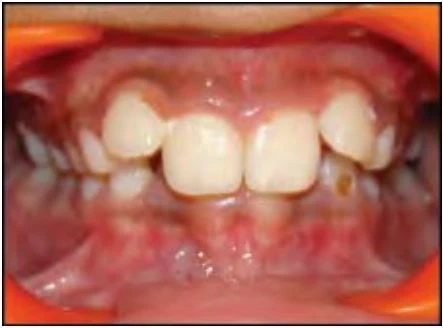

2.2 SAI KHỚP CẮN THEO MẶT PHẲNG ĐỨNG NGANG

Trường hợp này có thể chia làm hai phân loại tùy thuộc vào độ phủ theo chiều dọc của các răng giữa hai hàm.

Cắn sâu

Với loại này, độ cắn phủ theo chiều dọc giữa răng hàm trên và răng hàm dưới lớn hơn so với bình thường.